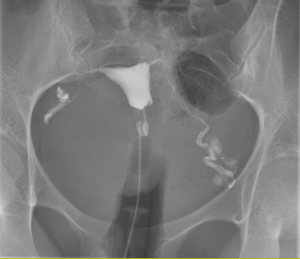

L’hématurie, qu’elle soit visible à l’œil nu ou uniquement au microscope, constitue unsymptôme à ne pas négliger. Derrière cette présence de sang dans les urines peuvent secacher des pathologies bénignes comme des affections plus graves, notamment tumorales.Le rôle de l’imagerie médicale est alors central, tant pour identifier l’origine du saignementque...